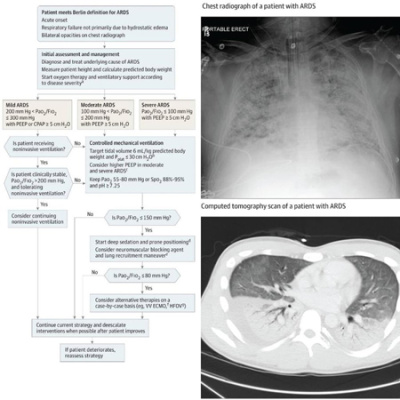

The ARDS in COVID-19 patients appears more responsive to PEEP and prone ventilation, but seems to require prolonged ventilation and may be associated with myocardial injury. Michelle N. Gong, MD, MS, Chief of Critical Care Medicine at Montefiore Medical Center in the Bronx, discusses her department's experience managing critically ill coronavirus patients, procuring diagnostic tests and personal protective equipment (PPE) for her staff, and more.